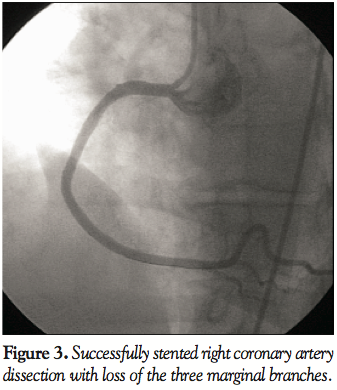

Case Report. A 42-year-old woman with hypertension presented with 8 months of typical angina. She was referred for an outpatient coronary angiography. The right dominant coronary artery showed no significant disease (Figure 1). Shortly after engagement of the left coronary artery, she developed chest pain, hypotension and new ST-segment elevation in both the precordial and inferior leads. Left coronary angiogram revealed TIMI 3 flow without any evidence of complications, including dissection or thrombosis. Left ventriculogram showed normal left ventricular ejection fraction (LVEF) without any wall motion abnormalities. Symptoms and ST-segment elevation persisted. Repeat RCA angiogram showed an extensive spiral dissection extending from the ostium to the distal RCA, with flow-limiting occlusion in the 3 marginal branches (Figure 2). The dissection was successively treated with direct stenting with 3 bare-metal stents (Figure 3).

The patient left the catheterization laboratory with minimal residual chest discomfort and significant resolution of the ST-segment elevation. Two-dimensional echocardiography showed normal LVEF with no evidence of right or left ventricular wall motion abnormality.